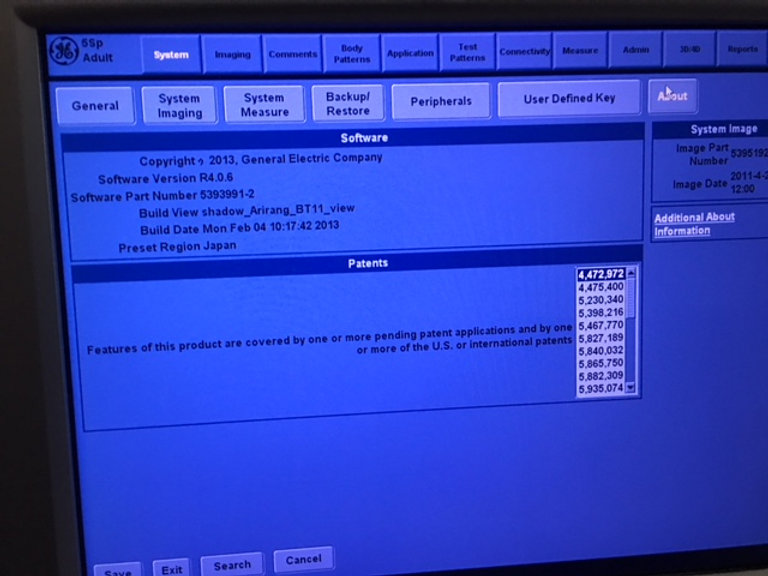

GE Logiq P5 d’occasion Lieu : Australie (U3075) Fabriqué : Oct 2013 Version du logiciel : R4.0.6 Options installées : Basic, Anatomical M, Cross Beam, SRI, Auto Sondes IMT : 5Sp, 8C, 11L